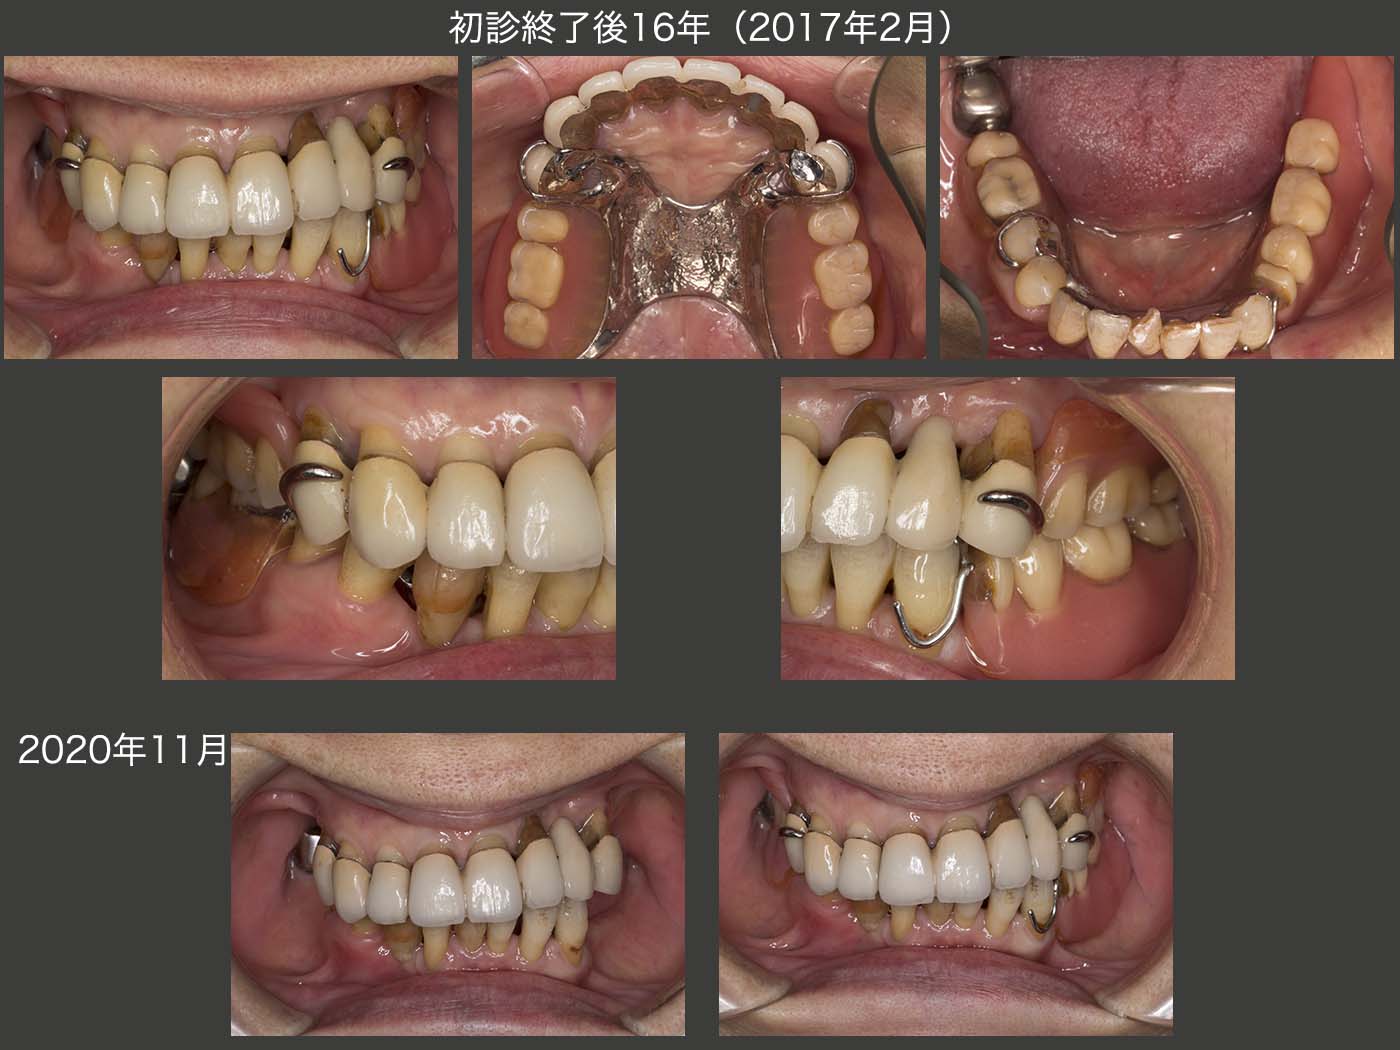

2017年2月,初診終了後16年の状態.スライド5で述べたマイナーチェンジを時々行ったが,全体としては良好に推移している.特に,メタルボンド冠で連結固定した上顎の残存歯が,まだ十分に機能していることに驚いている.

初診終了後16年の義歯装着の状態.レストの適合は16年の月日が流れたとは思えないぐらいに良い状態である.特に上顎義歯は,下顎の残存歯と咬合していないのが故に,顎堤の吸収が生じなかったと考えている.(残存歯による加圧要素がないと,顎堤は吸収しにくい.)もちろん,上顎義歯はこれまでに一度もリライニングを行っていない.

スライド下段に示す,初診終了後約20年の2020年11月の状態であるが,右下2の動揺が大きい以外は,大変良好である.